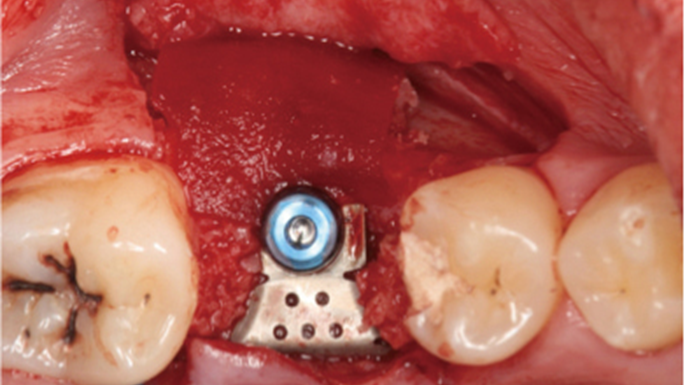

“Thin ridge expansion with minimally invasive surgery!

Use SmarThor & AnyRidge to place a wider diameter implant with minimal drilling after ridge splitting, even in thin ridge under 2mm! “

Clinical case: Ridge splitting technique using SmarThor + AnyRidge as expander

- Courtesy of Dr.Kwang-Bum Park, Korea -

AnyRidge, ridge splitting, GBR, Dr. Kwang-Bum Park, mandibular posterior, SmartThor, Mega-Oss, thin ridge, bone regeneration

AnyRidge implant system. SmarThor, Mega-Oss